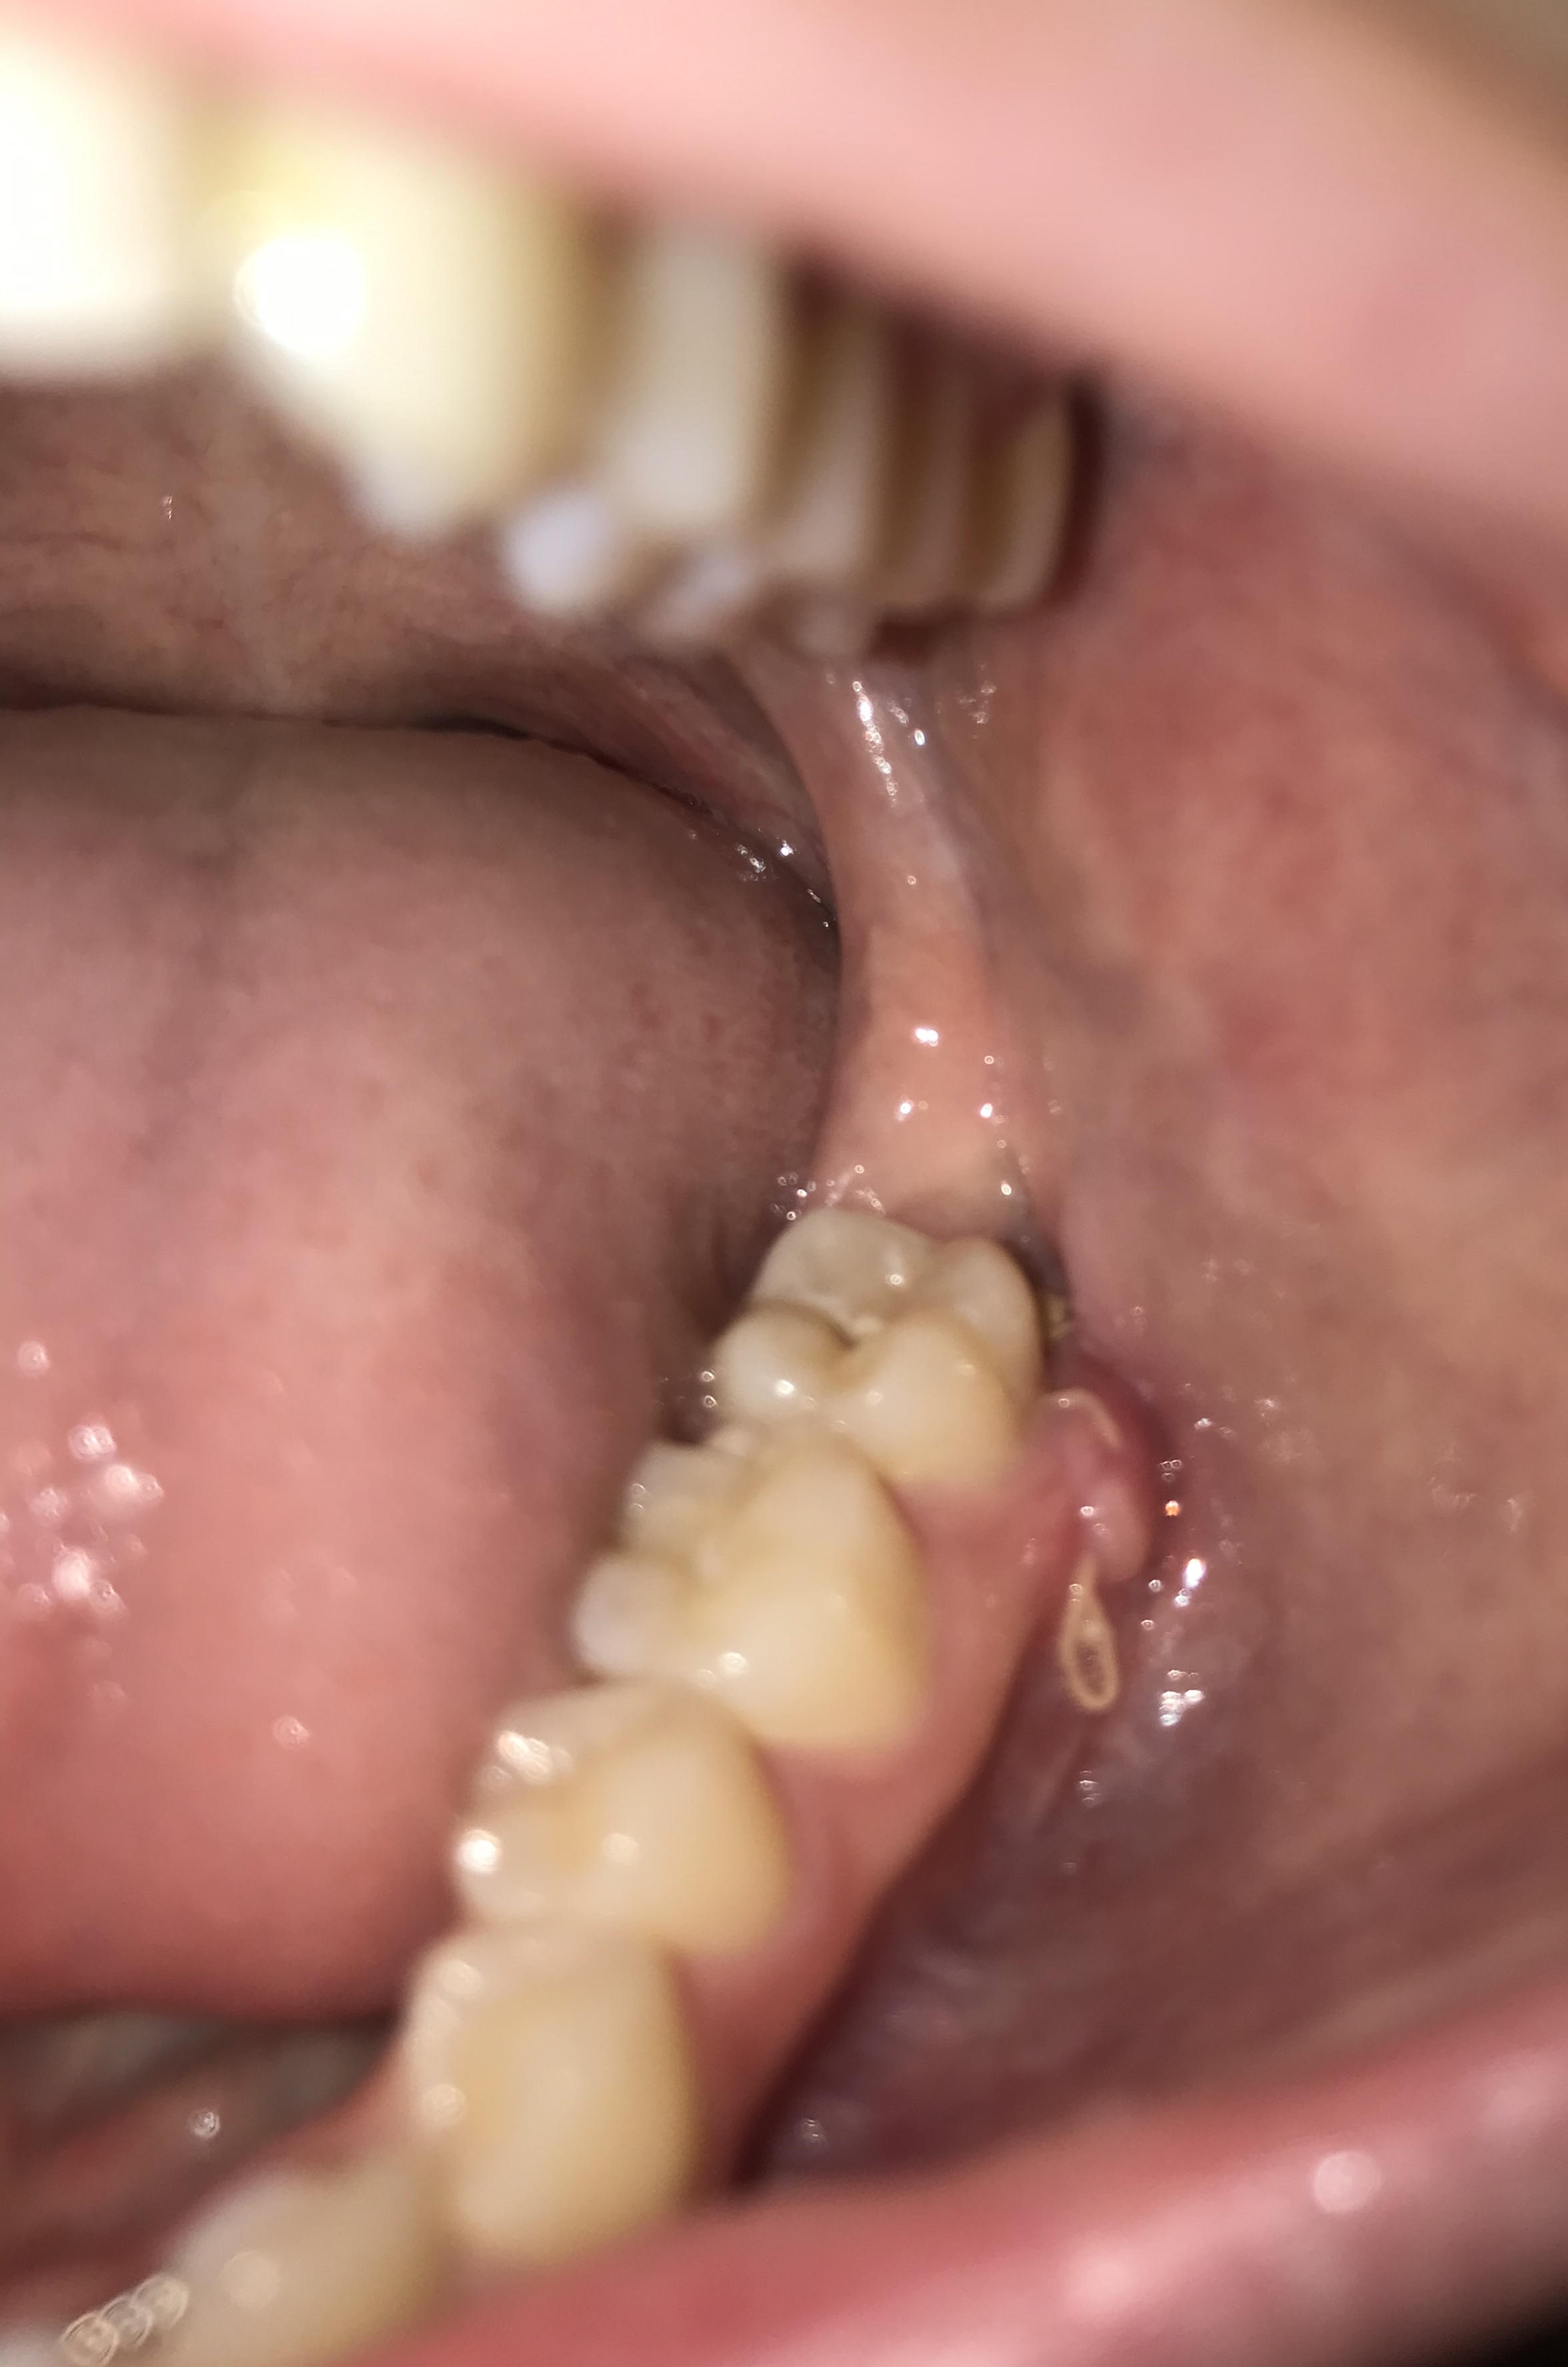

twee weken geleden heb ik 3 verstandskiezen aan de linker kant laten trekken, 2 van boven en 1 onder bij de kaakchirurg. De behandeling ging goed, ik heb er nu alleen nog een bult zitten met een hechting erin. De bult zit niet op de plek waar mijn verstandskies heeft gezeten maar onder de kies die daarvoor zit, een paar dagen nadat ze getrokken waren viel het mij op.

De bult heeft dezelfde kleur als mijn tandvlees, bij de rand wat roder dan derest. Verder is het niet heel groot maar het valt wel op als je er naar kijkt, de bult voelt een beetje hard aan en kan het ook niet indrukken.

Nu inmiddels alle hechtingen eruit zijn voel ik ook een bult helemaal linksbovenin, volgensmij op de plek waar mijn bovenste verstandskies heeft gezeten.. Ik kan die bult niet zien omdat hij helemaal bovenin/achterin zit, voelt wel hetzelfde aan als de andere bult.